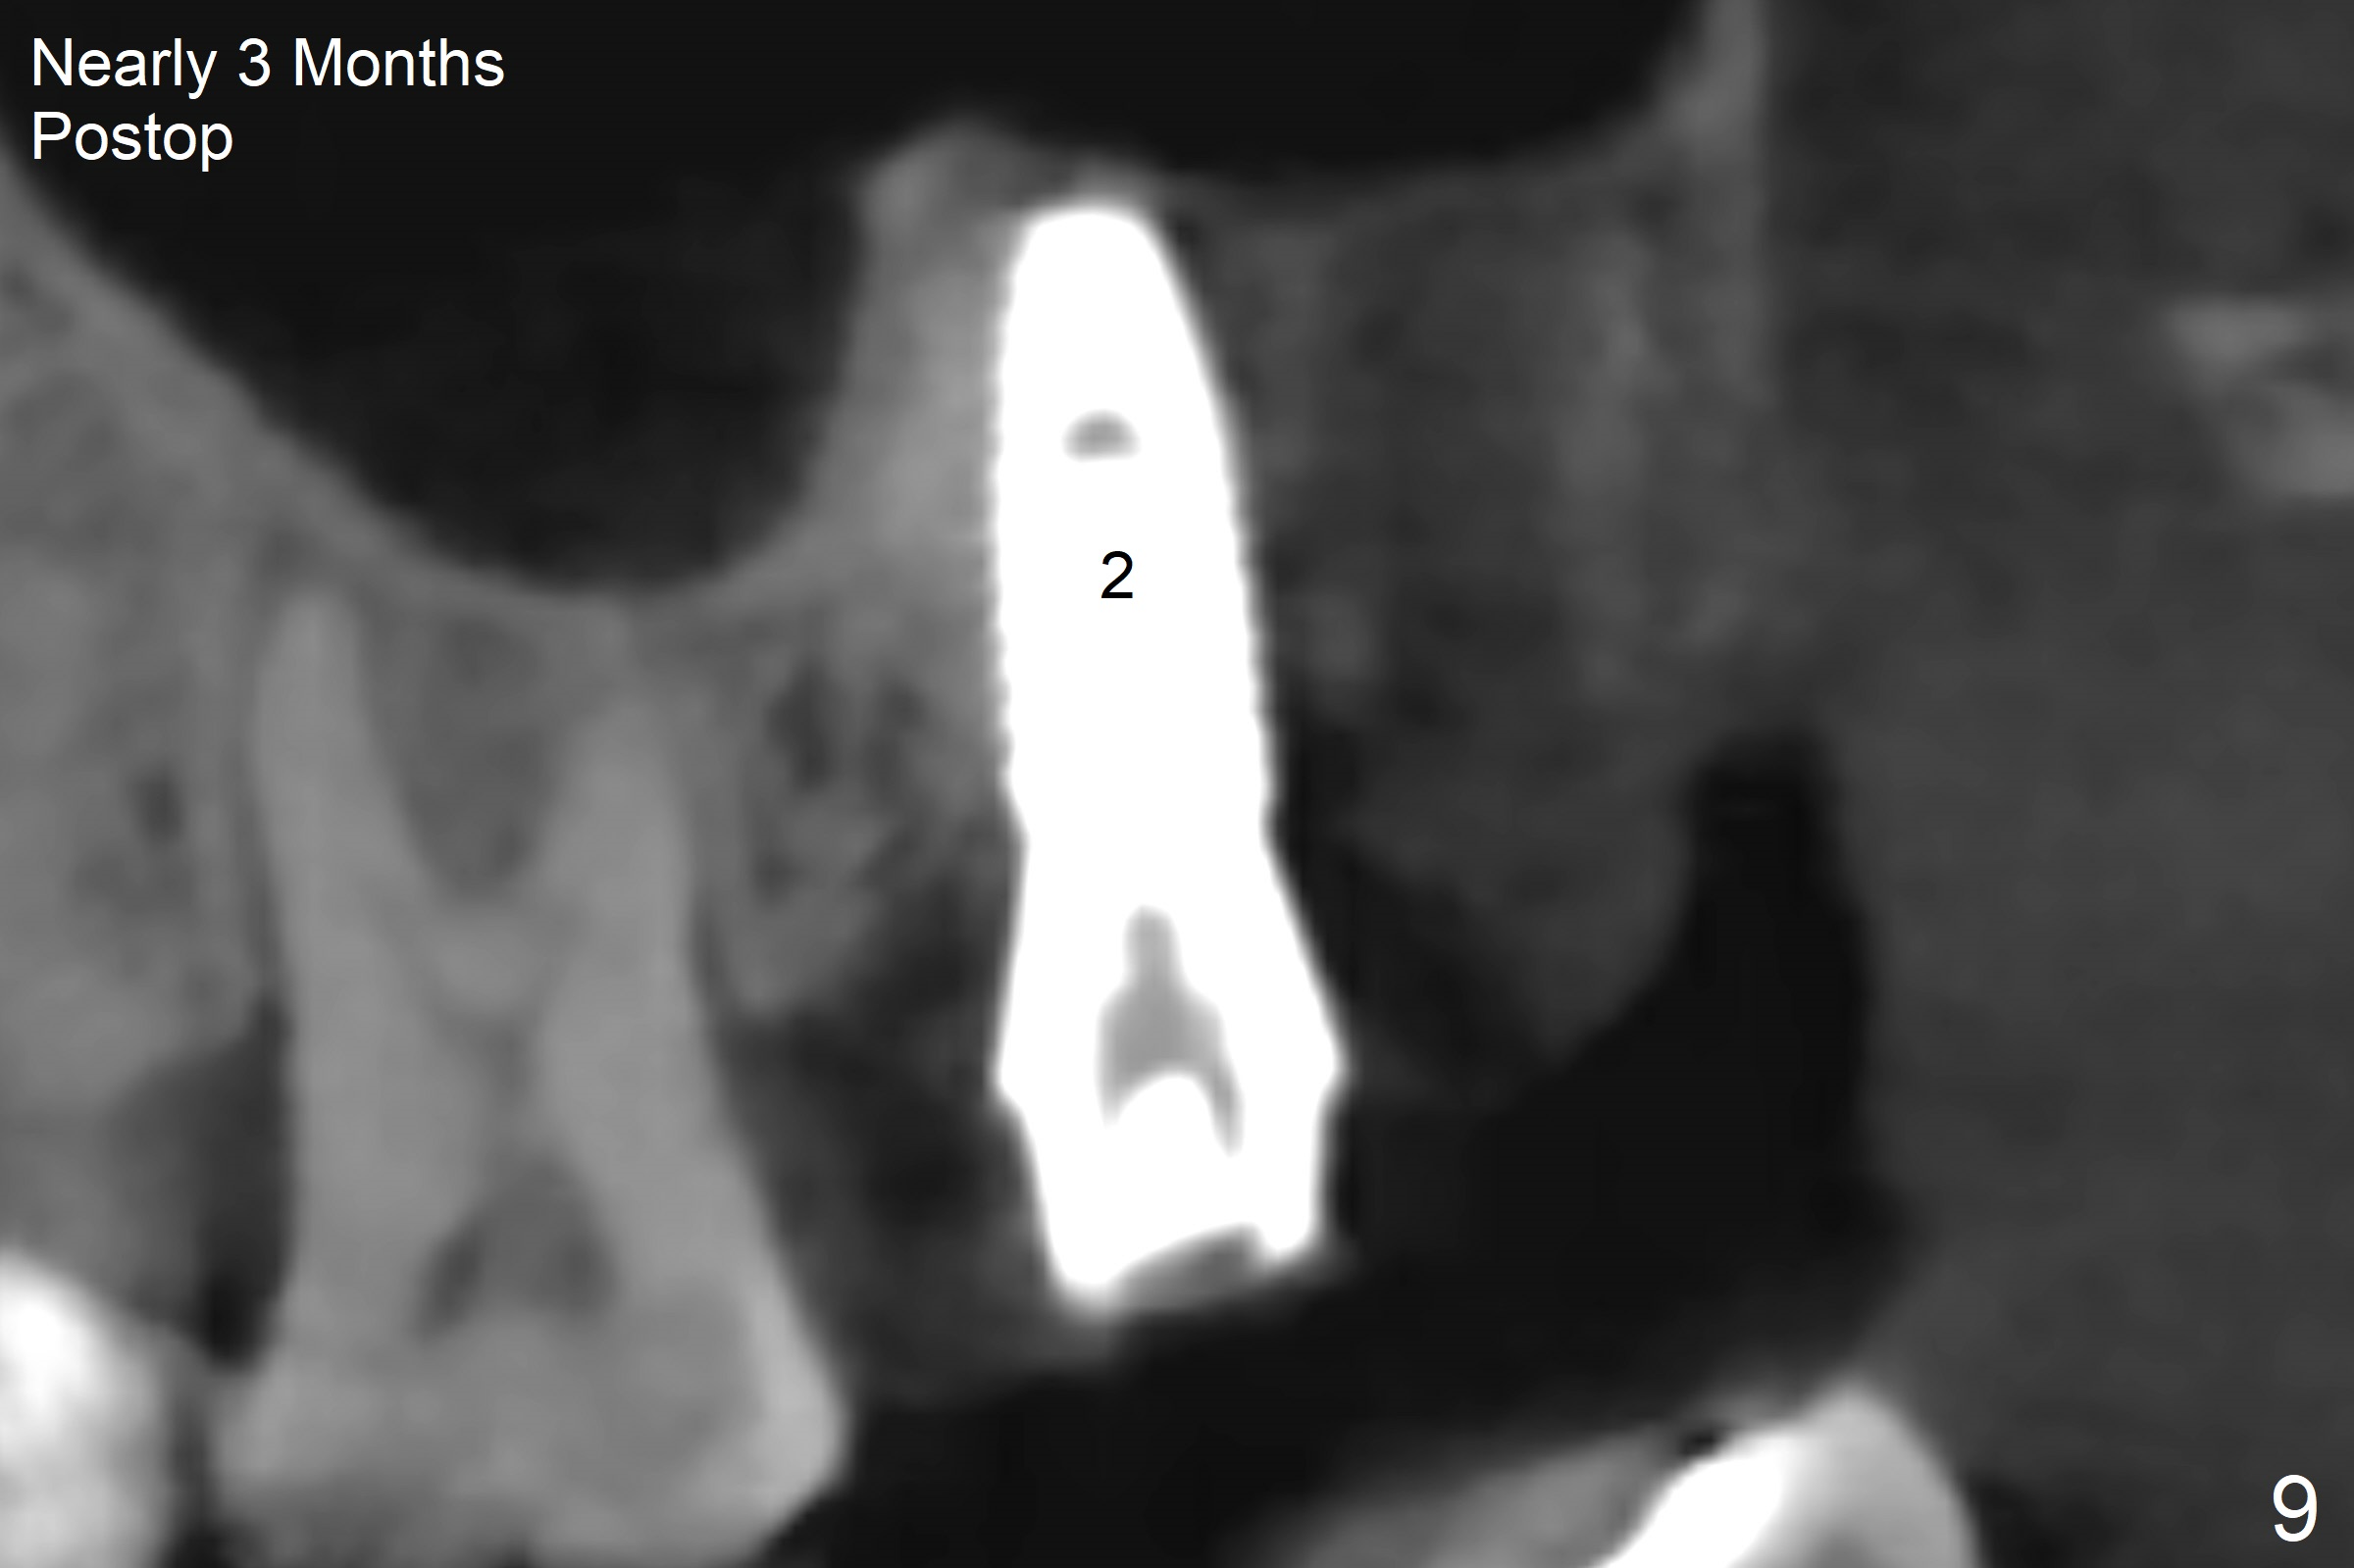

After extraction of the 3rd molar with mesial periodontal defect, osteotomy for 2nd molar implant is initiated in the mesial slope of the 3rd molar socket (Fig.1 red dashed line). When osteotomy is finished with IS drills and sinus lift with Magic Sinus Lifter (S-reamer with 11 mm stopper being short), a 4x10 mm dummy implant is placed with ~ 4 implant thread exposure (Fig.3). Following use of Lindamann bur to move osteotomy mesial and larger drill, a 4.5x10 mm implant is placed with 5-7 implant threads exposed distally (Fig.4,7 (~ 50 Ncm)). The bucco(B)-palatal(P) extent of the implant thread exposure is larger (Fig.5) than that associated with the 4 mm dummy implant (data not shown). The exposed implant surface is covered with Vera Graft (Fig.7*), Collagen plug and an immediate provisional after adjustment of abutment height (Fig.6,7). The bone density distal to the implant is low 3 months postop (Fig.8,9 CBCT) and 3.5 months postop (Fig.10,11). The permanent crown is cemented nearly 4 months postop. The distal cortical bone contacts the implant (Fig.12 ^), while the mesial bone increases in density (*) 2 years postop.